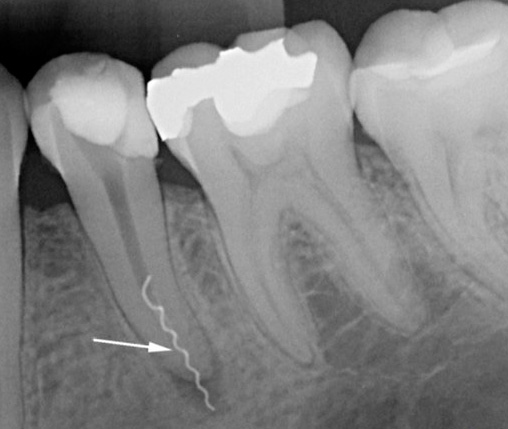

Nesta foto, você pode observar como o dente cuida do tratamento da pulpite usando o método resorcinol-formalina (amputação desvital):